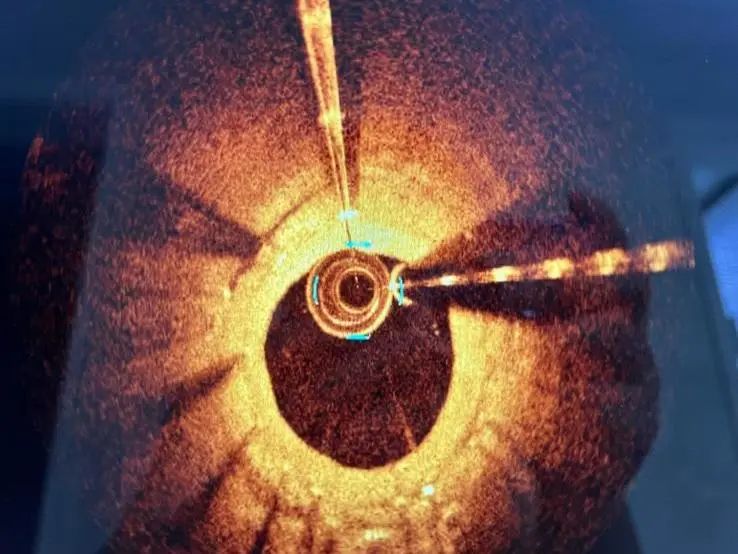

术中造影和OCT

LAD支架内再次发生狭窄伴明显钙化影像,刘长乐主任手术团队考虑LAD已经两层支架植入术后,当即决定手术策略:在OCT指导下使用shockwave冲击波球囊进行治疗。

术前OCT评估最小管腔面积(MSA)为2.48mm²,狭窄处为双层支架金属影,增生斑块为明显环形钙化病变。选用shockwave 3.0×12mm球囊实施钙化斑块碎裂术。

术中连续治疗8个周期(80次脉冲)后,复查OCT可见钙化处内膜至支架梁间的明显裂隙,震波深度达0.49mm,钙化环被打开。换用3.0×15mm NC高压球囊18-20atm充分扩张。

术后运用OCT测量评估,MSA恢复到4.86mm²,治疗前后造影对比,病变扩张满意,支架内狭窄基本消失,TIMI血流3级,患者无不适主诉。